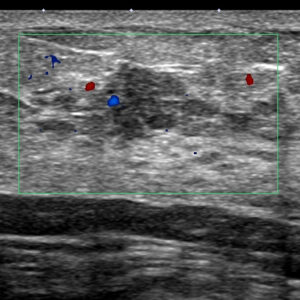

症例1 明らかに「癌を疑うべき」症例

カテゴリー3ではなく、5(もしくは4)をつけるべき

「不整形」「前方境界線断裂」という2点からは、5とすべきと思いますが、4でも許容されるのは、その「サイズ」が原因となります。

これは「私category」では6(乳癌の可能性がかなり高い)となります。

♯前方境界線断裂に見えるので7(乳癌といいきれる)にしたいところですが、(そのサイズにより)実際に患者さんにも「乳癌の可能性が高いです」とは言いましたが、言い切りませんでした。

2つのシコリ(実際は全体像をみて行くと繋がっている部分がありそう)の1個1個が5~6mm,どうしてもエコー像では「小さいと」それが理由にカテゴリーが落とされる(良性よりとなる)傾向にあります。

これをカテゴリー3としていますが…

この不整形、及び前方境界線断裂で明らかに「癌」の所見です。